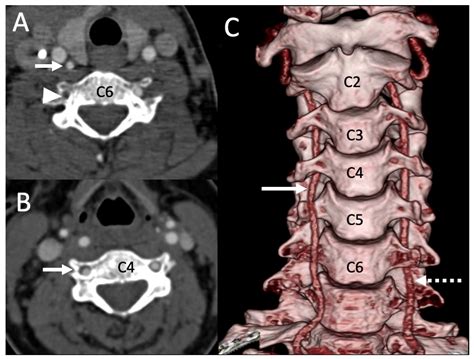

• CT Angiography (CTA): This provides a detailed 3D view of the blood vessels in the neck and brain, identifying blockages quickly.

It is important to note that vertebral artery dissection—a tear in the inner lining of the artery—is a specific type of injury that often leads to clot formation. Unlike slow-forming plaque, a dissection can happen rapidly, making it a critical consideration in younger, otherwise healthy individuals who experience sudden neck pain and stroke symptoms.